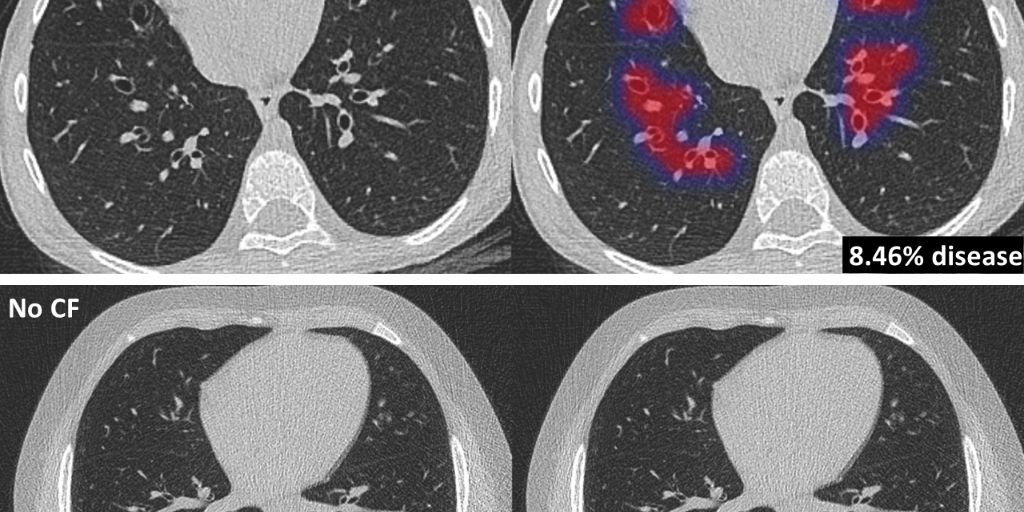

The new AI-based algorithm PRAGMA-AI, part of Thirona’s lung quantification software package LungQ, automatically identifies lung abnormalities related to CF, such as abnormal airways and collapsed lung tissue. These measurements supply sensitive and objective information on the pattern and extent of CF lung disease. This is critical information, allowing clinicians to monitor disease progression and supporting clinical decision-making for treatment plans. LungQ PRAGMA-AI has been validated on a large number of scans of CF patients, showing high diagnostic performance comparable to trained human analysts.